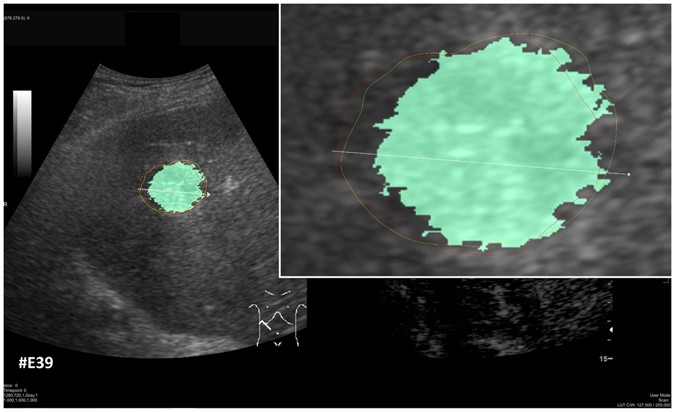

Figure 16

Direct comparison of our approach with GrowCut (green) for case 39. The red outline represents the manual segmentation including the white arrow representing the manually drawn maximum diameter. The yellow line represents the result of the semi-automatic segmentation (see also Fig. 11). Compared with the manual segmentation, our semi-automatic segmentation algorithm could achieve a DSC of 92.47%. However, compared with the manual segmentation, the GrowCut-based segmentation achieved a DSC of 85.46%.